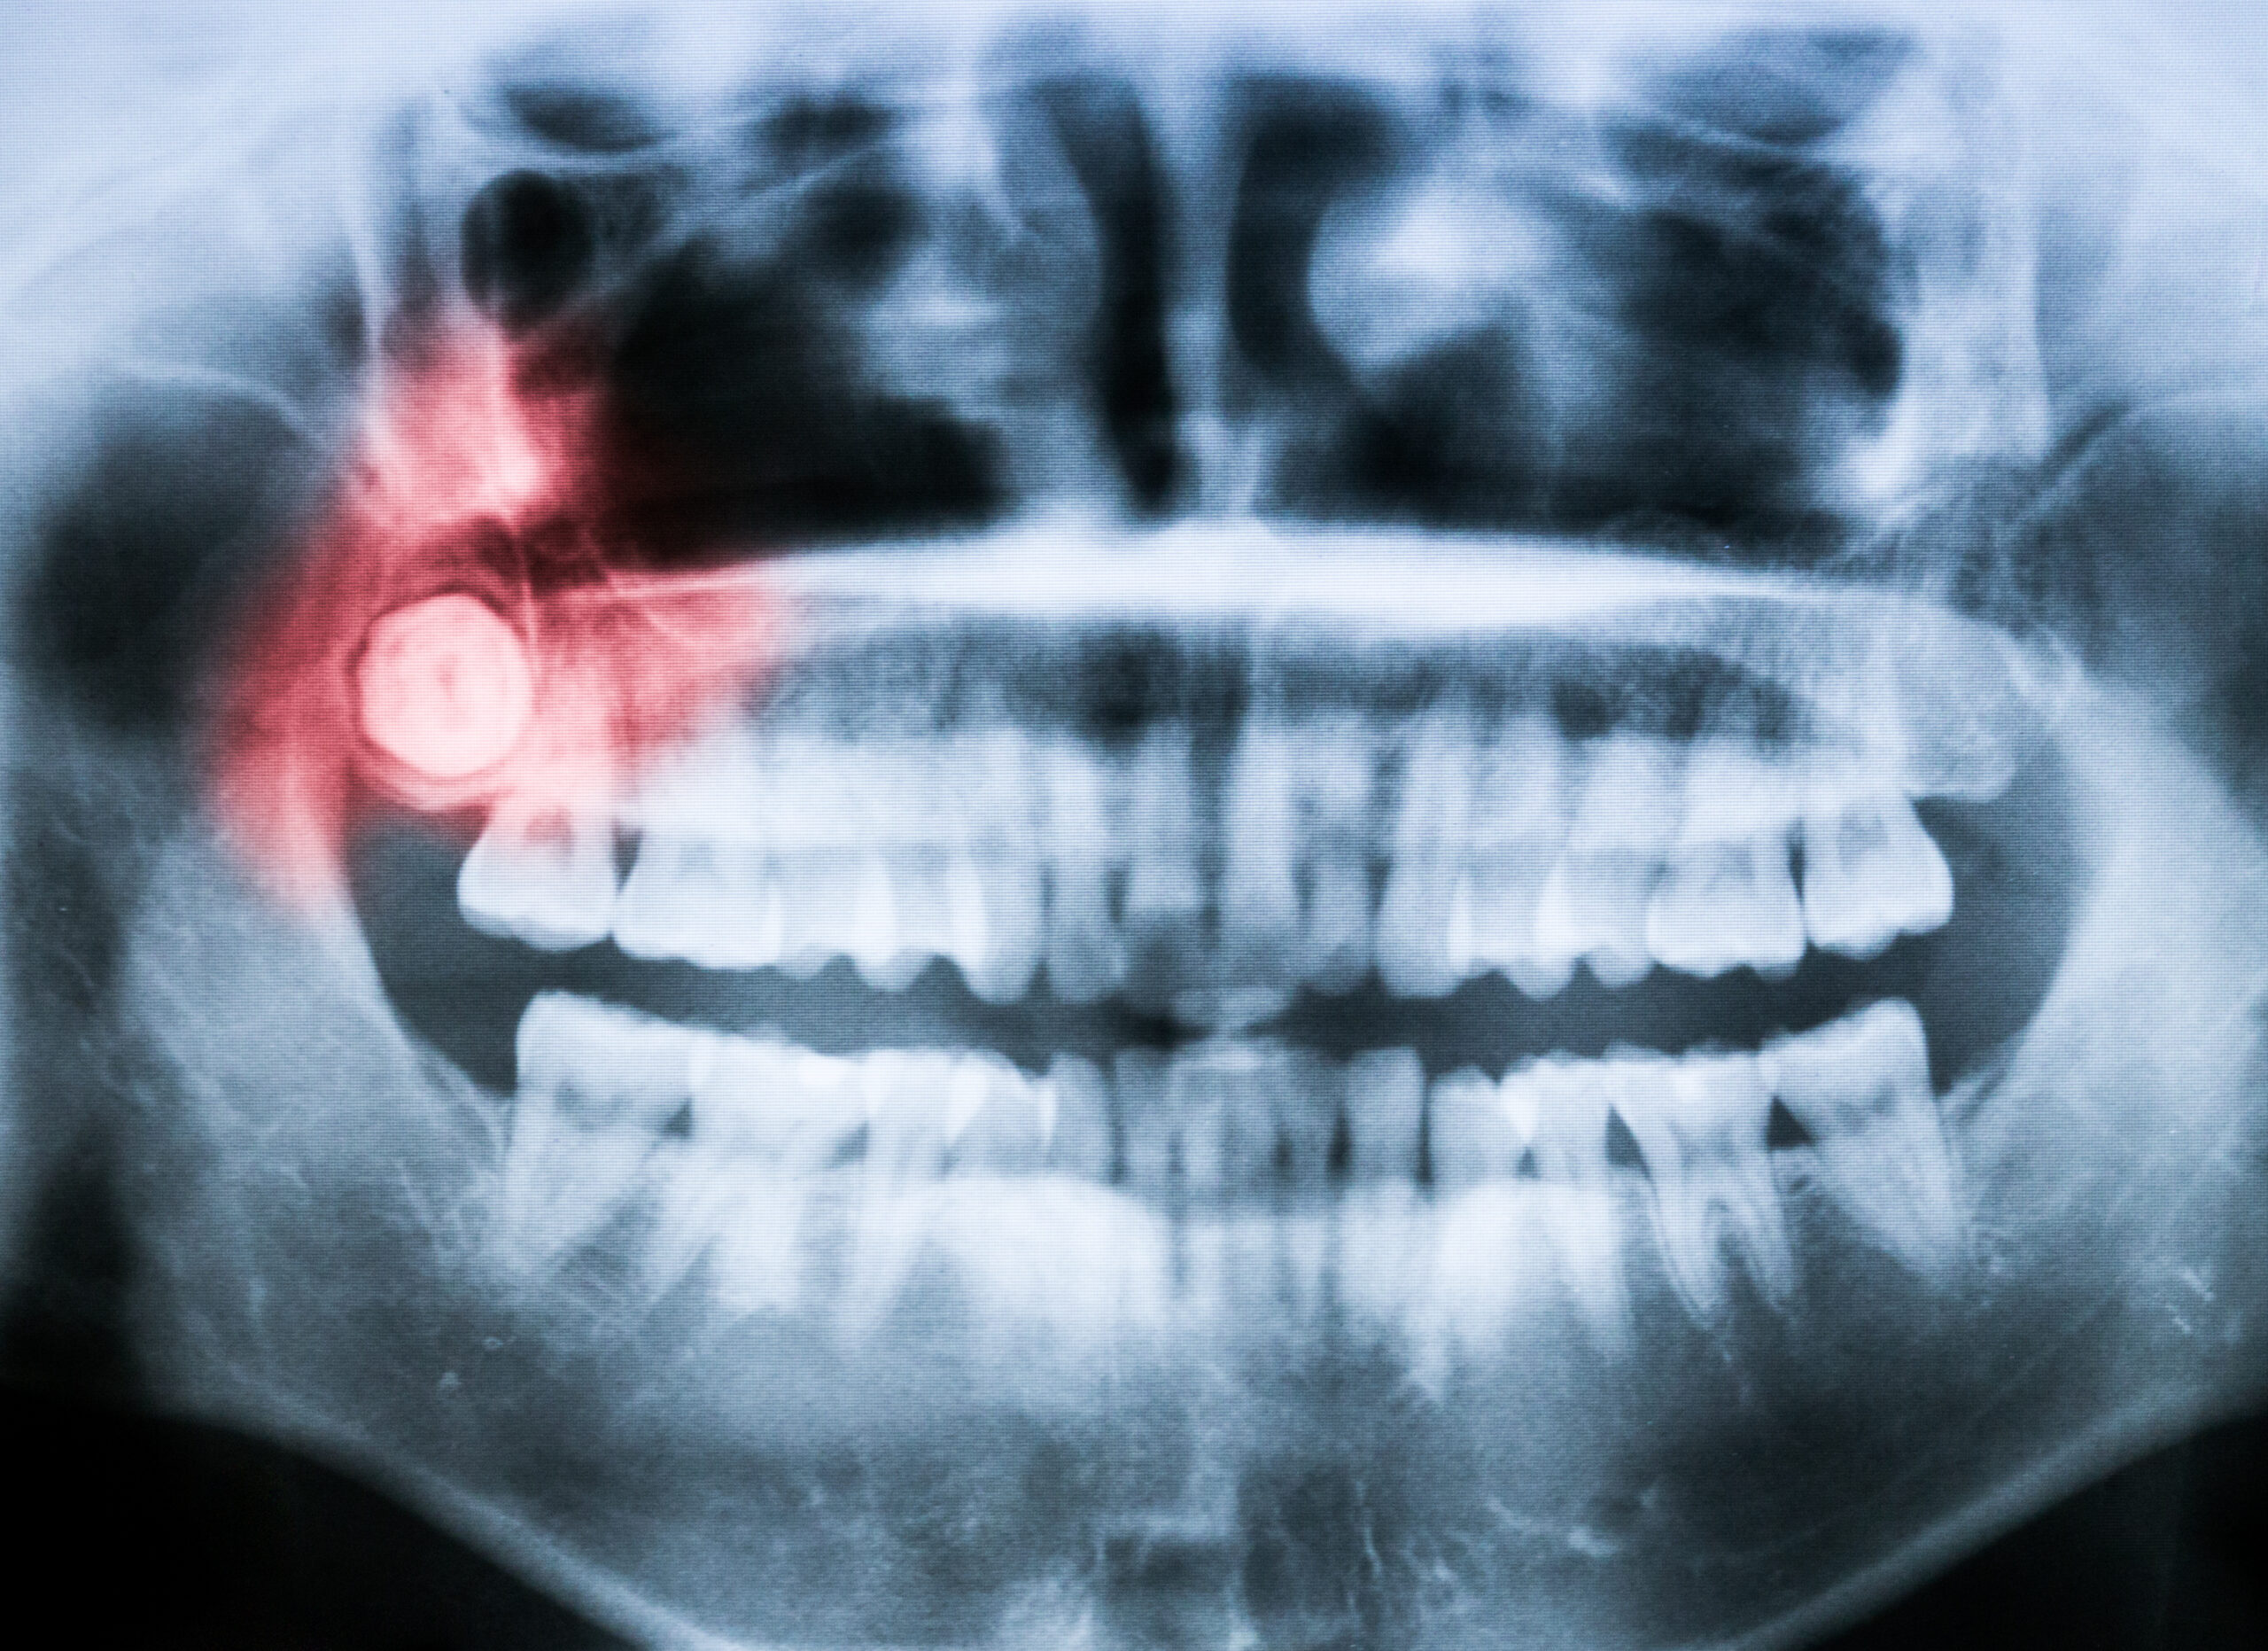

x-ray of impacted wisdom tooth

Wisdom teeth are often painful, but they often don't need to be removed. Deposit Photos